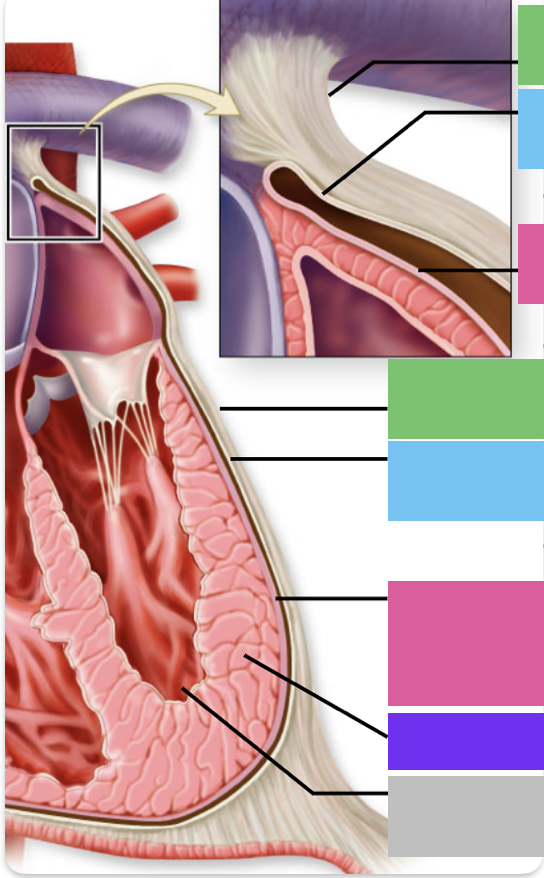

fibrous pericardium

blue

parietal pericardium

pink

visceral pericardium (connective tissue) / epicardium (muscle)

purple

myocardium

grey

endocardium